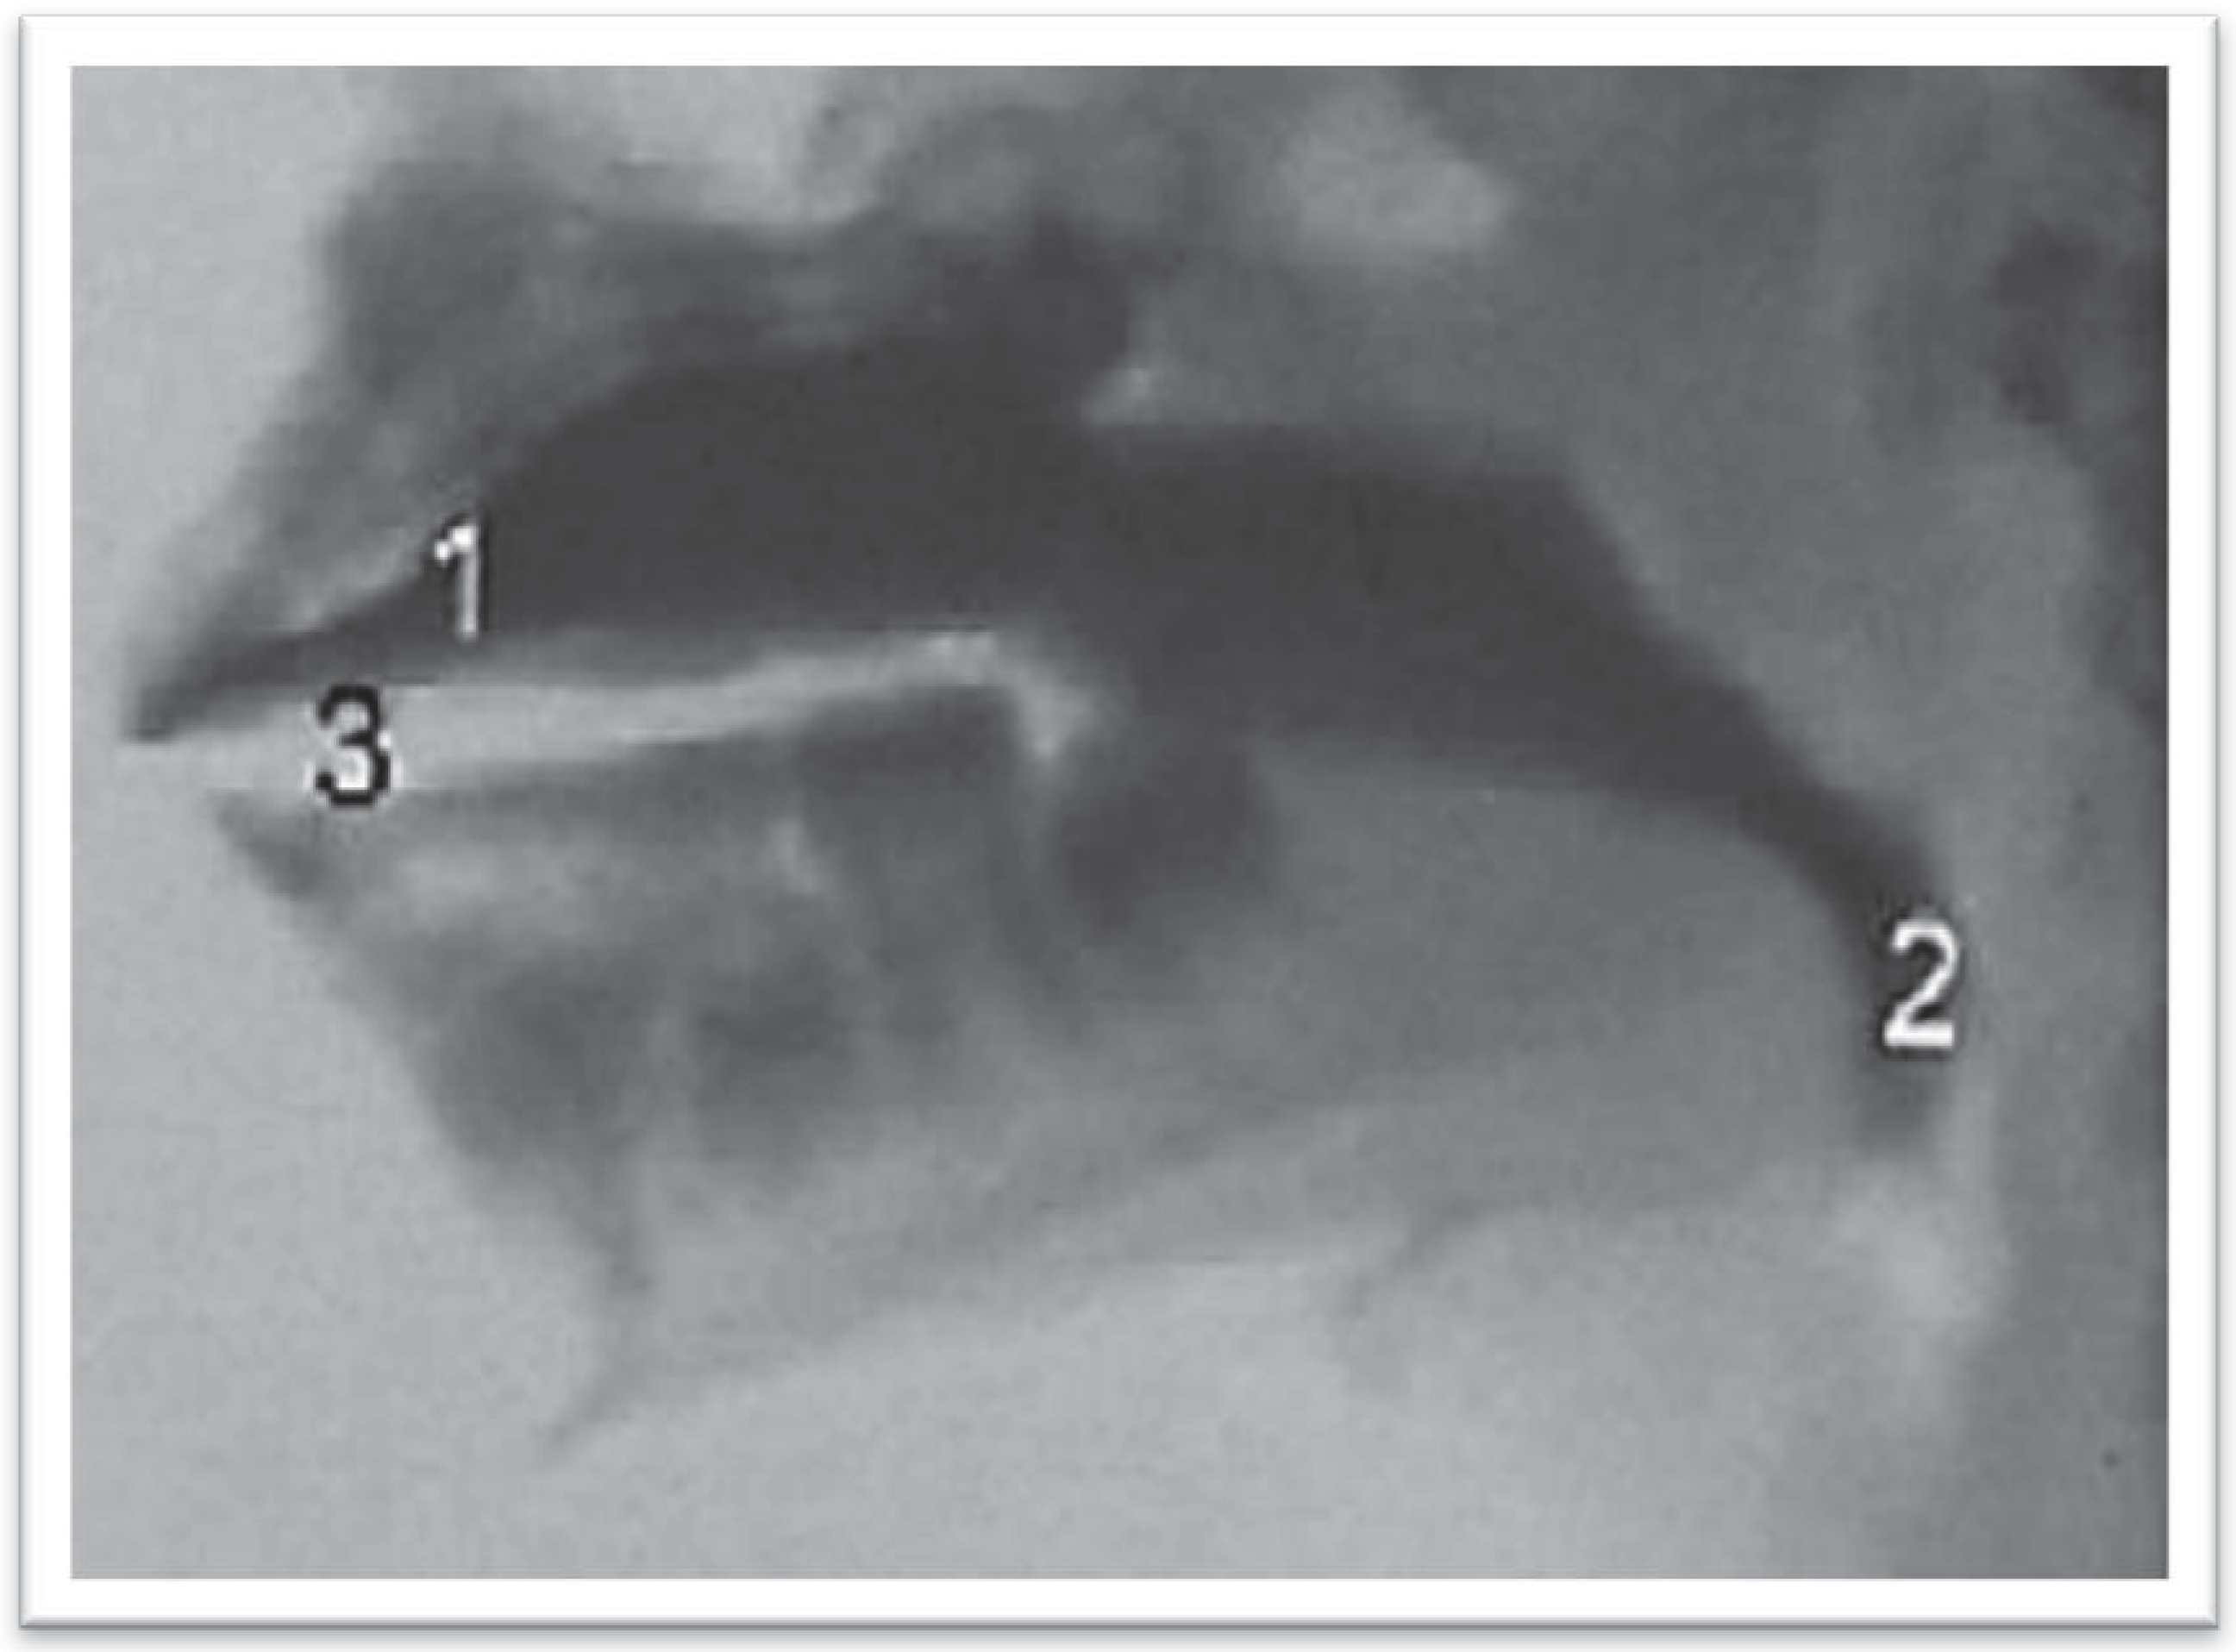

Dodds et al. (1989) found that 72% of the participants with normal oral motor function used the Tipper type of swallow, and 19% used the Dipper type of swallow. In the present study subjects the Tipper (Dodds et al., 1989; Logemann, 1993, 2007; Logemann, Pauloski, Rademaker & Kahrilas, 2002) swallowing type occurred in 94.87% (Figure 1A,B) of the children with normal dental occlusion, while the Dipper (Dodds et al., 1989; Logemann, 1993, 2007; Logemann et al., 2002) swallowing type occurred in 2.56% of the swallows. In 2.56% of the swallows, the observation of the oral phase indicated swallowing with premature loss of the liquid consistency bolus, consistent with the description by Logemann (1993, 2007), Logemann et al. (2002).

Figure 1. Normal swallowing occurred in 94.87% of the gulps in children presenting normal occlusion. (A) Videofluoroscopic exam on individuals with normal dental occlusion during oral organization phase. 1—Contrasted solution organized on the dorsal surface of the tongue. (B) Videofluoroscopic exam on individuals with normal dental occlusion during oral ejection phase. 1—Beginning of the projection of the bolus to the pharynx.